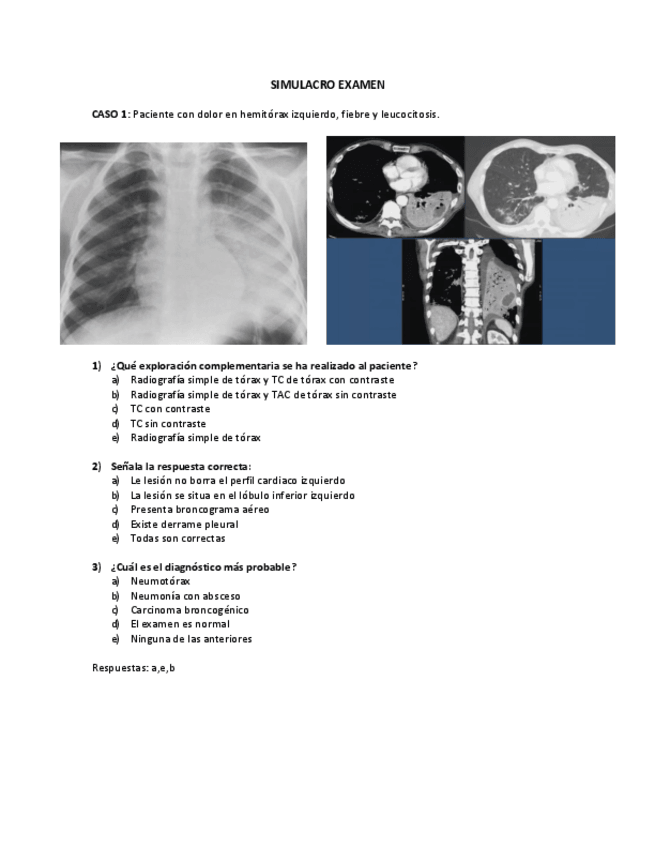

SIMULACRO-EXAMEN.pdf